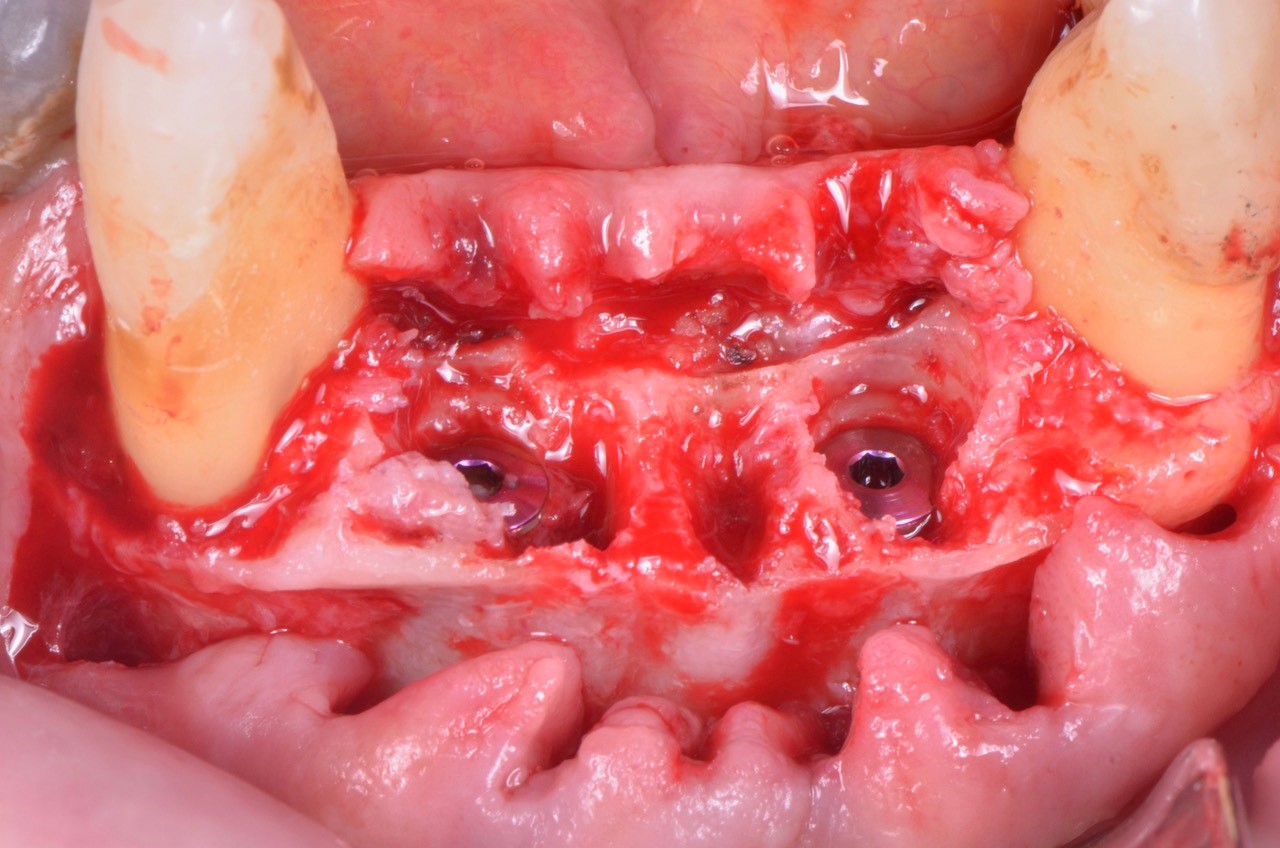

Posizionamento sub crestale di due V3

Foto: Posizionamento subcrestale di due impianti MIS V3